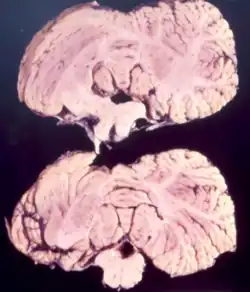

Bei Kuru handelt es sich um eine unheilbare Prionenkrankheit, die im 20. Jahrhundert endemieartig beim Volk der Fore in Papua-Neuguinea und in geringerem Ausmaß bei einigen Nachbarvölkern auftrat. Kuru ist eine Form der Transmissiblen spongiformen Enzephalopathie, die durch die Übertragung von abnormal gefalteten Proteinen (Prionen) verursacht wird.[1][2] Das Wort Kuru stammt aus der Sprache der einheimischen Bevölkerung und bedeutet Muskelzittern.[3]